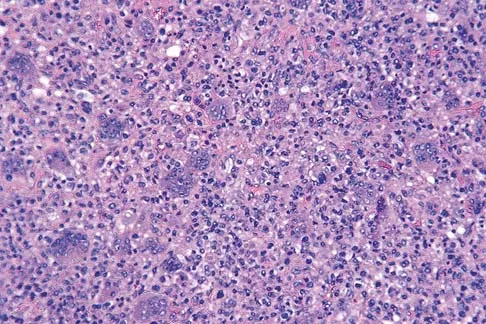

A 9-year-old boy has a painless enlarged mass on the dorsum of his hand. Figures 14a through 14d show the clinical photograph, radiographs, and biopsy specimen. What is the most likely diagnosis?

A 13-year-old boy has knee pain after sustaining a mild twisting injury while playing basketball 4 weeks ago. Radiographs and MRI scans are shown in Figures 24a through 24d, and biopsy specimens are shown in Figures 24e and 24f. Treatment should consist of